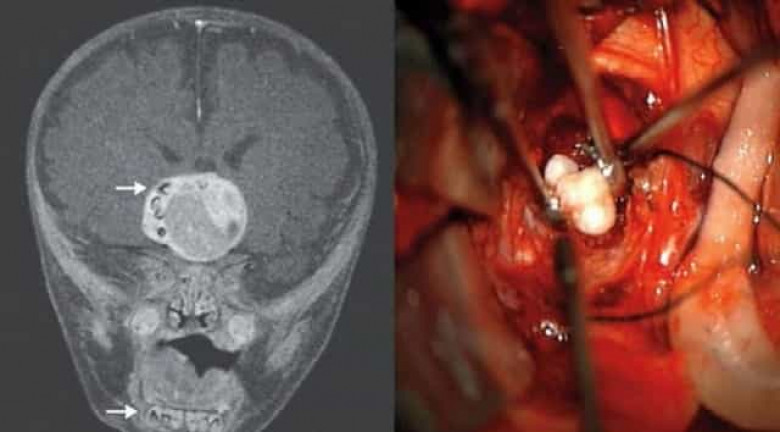

Ատամներ ուղեղում

ԱՄՆ-ում բժիշկները 4 ամսական երեխայի ուղեղից ուռուցք են հեռացրել, որում հայտնաբերել են մեծ քանակությամբ ձևավորված ատամներ։ Հետագայում պարզվել է, որ ուռուցքն առաջացել է ատամների բջիջներից, ինչի արդյունքում էլ առաջացել են ատամները։